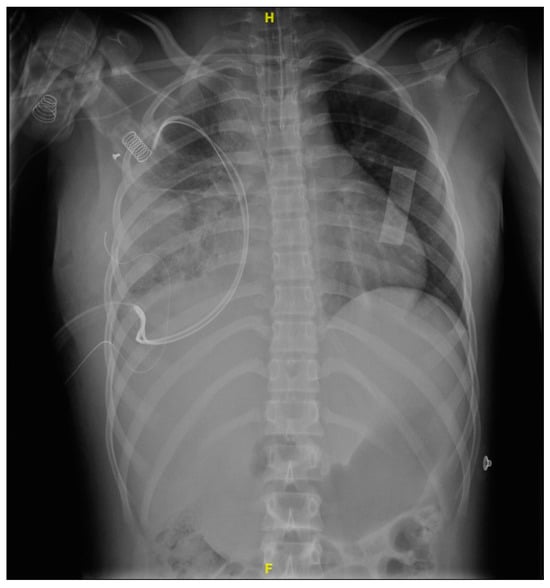

Upon admission to the emergency department of our hospital, she scored 15 on the Glasgow scale, requiring oxygen support with a face mask at 10 L/min, presented polypnea, the right hemithorax amplexation was decreased, and oxygen saturation of 89%. In addition, the right pleural tube showed 370 mL of hematopurulent output with a total of 128 mL (2.9 mL/kg/h) in 24 h. The gasometric study at the intake showed acid–base balance, hypoxemia, and normolactatemia (Figure 1).

Figure 1. Anteroposterior thoracic X-ray taken on admission shows a right pleural tube and right pleural effusion with loss of the costophrenic angle and radiopacity in the right lung.